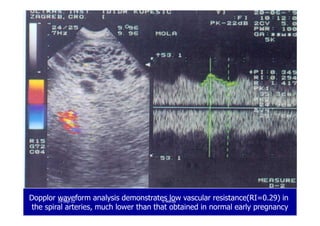

Dopplor waveform analysis demonstrates low vascular resistance(RI=0.29) in

the spiral arteries, much lower than that obtained in normal early pregnancy